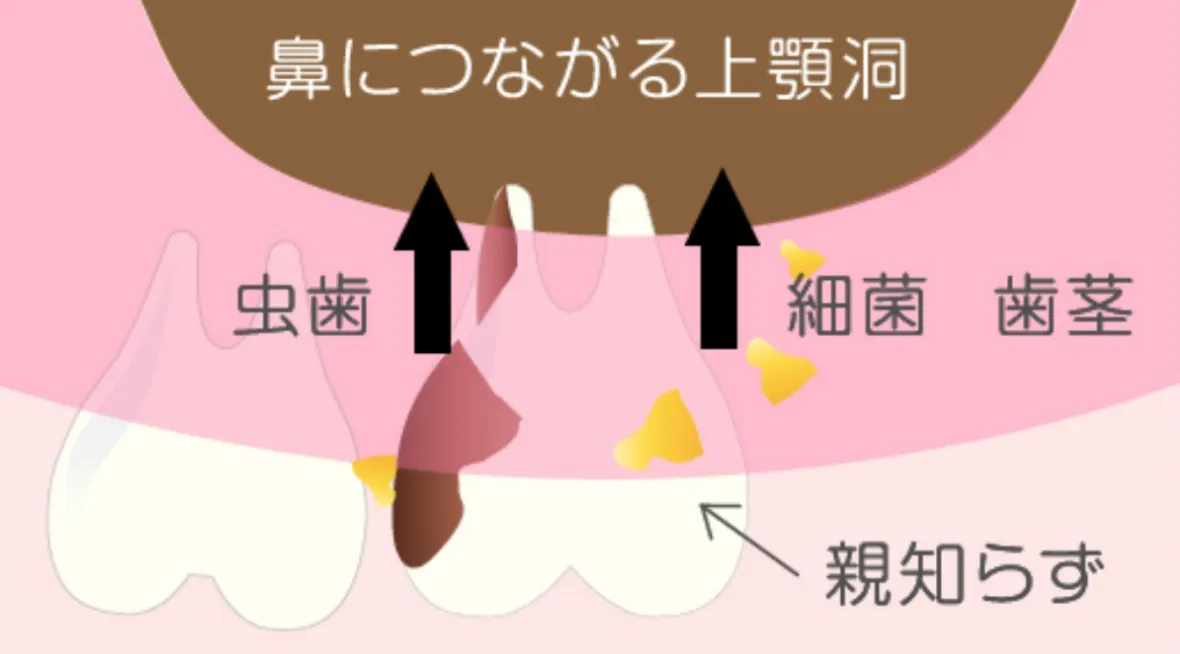

上の親知らずの場合

歯の根が深い位置にあると、上顎洞(じょうがくどう)という鼻につながる空洞に近くなり、この状態で虫歯や口内の細菌の感染があると、歯が原因の蓄膿症 (ちくのうしょう)になり、鼻の手術が必要になる事があります。